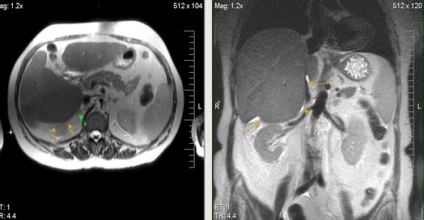

Több májáttétek.

Egyedi kis májáttétek; hasonlóság a natív vizsgálat hemangiomas.

Ugyanez a beteg. Postkontrastnye tomográfia. Egyedi kis májmetasztázisok ellentétben hemangiomas tomogramjait a korai és a késői fázisban válik parenchymás hypointense a natív vizsgálat (gyors enyhülést kontraszt kritérium 1 perc).

Áttétek a májban, a jobb vesét.